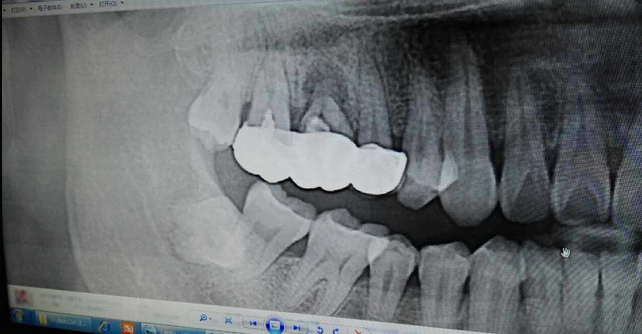

超聲牙周刮治案例

病例:患者男性47歲

右下8骨埋伏并且黏連;從根分叉處通過;有彈性;術中看到神經(jīng)束

實在找不到;近中牙冠沒去干凈

像這種不切除的牙冠,以后吸收的可能性不是很大,但有排除的可能性,自己自行排出,要是牙根的話吸收的可能性比較大

像這種沒有癥狀的殘留牙體組織不用去除可以吧